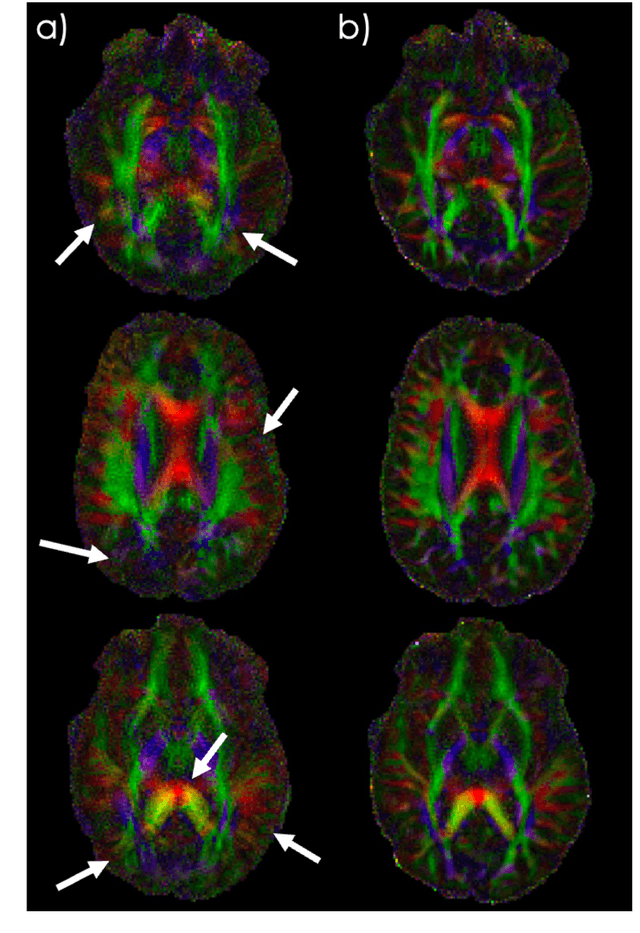

Spatiotemporal magnetic field variations from B0-inhomogeneity and diffusion-encoding-induced eddy-currents can be detrimental to rapid image-encoding schemes such as spiral, EPI and 3D-cones, resulting in undesirable image artifacts. In this work, a data driven approach for automatic estimation of these field imperfections is developed by combining autofocus metrics with deep learning, and by leveraging a compact basis representation of the expected field imperfections. The method was applied to single-shot spiral diffusion MRI at high b-values where accurate estimation of B0 and eddy were obtained, resulting in high quality image reconstruction without need for additional external calibrations.